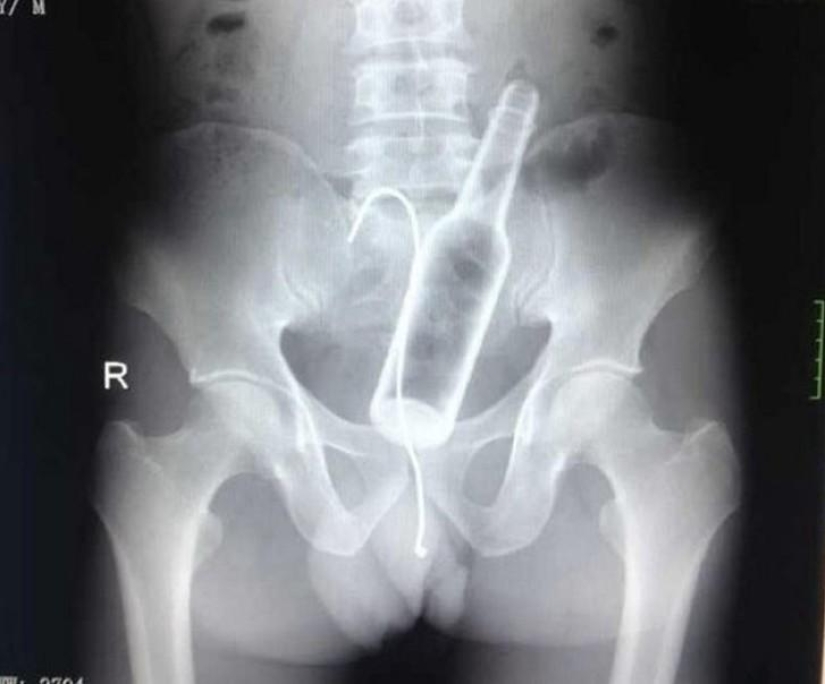

9. Botella.